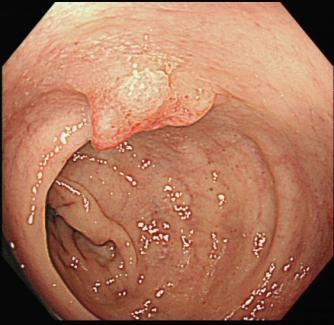

黄女士(化名)近一年来时常感到腹胀,近两周又出现了便血症状。她前往湖北科技学院附属第二医院消化内科就诊,行肠镜检查发现距肛门缘5厘米处有一个直肠息肉,怀疑早期癌变。

消化内科团队为其行进一步超声内镜评估显示,病灶尚未侵及肌层,符合内镜下黏膜下剥离术(ESD)指征。

在省人民医院专科联盟指导下ESD手术顺利完成,为什么“完整剥离”如此重要? 因为只有这样,才能将病灶连根拔起,并获取完整的病理标本,为后续的诊断和治疗提供最可靠的依据。也避免了外科开腹手术。

黄女士成功接受了ESD手术。术后病理分析证实了术前的判断:绒毛状管状腺瘤,局灶高级别上皮内瘤变。